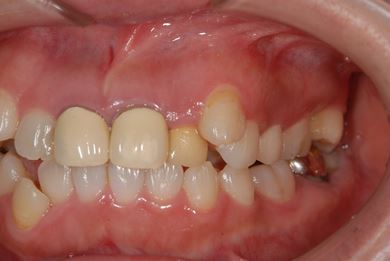

| 性別/年齢 | 女性 / 31歳 | ||||||||||||||||||||||||||||||||

| 治療方針 | セラミック治療により、審美的回復を行う。 | ||||||||||||||||||||||||||||||||

| 治療内容 | CAD/CAMオールセラミッククラウン1本(オールセラミック用土台1本)、オールセラミッククラウン2本(オールセラミック用土台2本) | ||||||||||||||||||||||||||||||||

| 総治療費 | 341,775円 | ||||||||||||||||||||||||||||||||

| 治療期間 | 10ヶ月 |